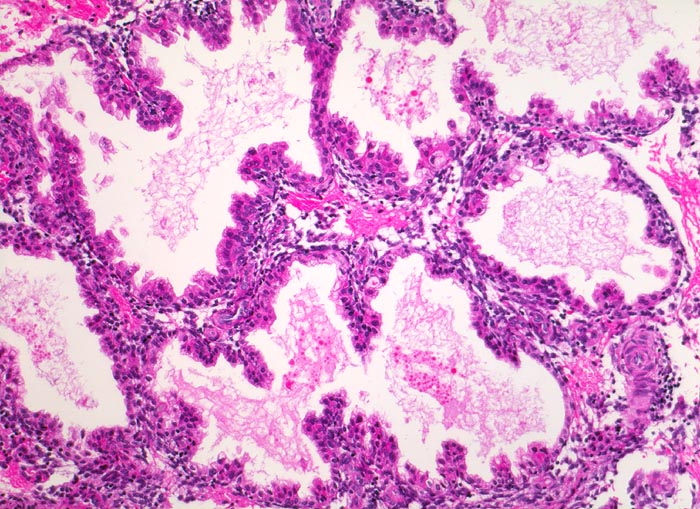

Morphologische Merkmale:

• Vergrösserte Plazentarzotten mit hydropischem Zottenstroma.

• Vereinzelt Zytotrophoblasteinschlüsse im Stroma.

• Vorwiegend einschichtiges Zytotrophoblastepithel ohne Atypien und mehrkerniger Synzytiotrophoblast. Physiologische polare Trophoblastproliferate.